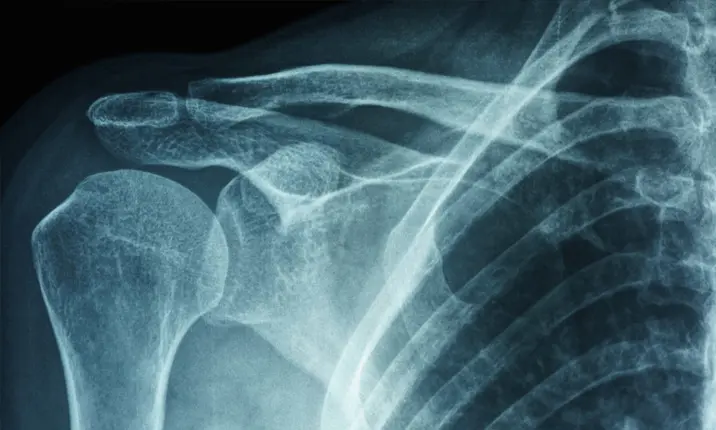

如果您出现肩周炎的任何症状,都应去看医生。医生会对您进行一系列检查,包括一般检查和病史讨论。医生还将对您进行运动评估。医生会要求您向不同方向移动肩膀,以了解肩关节受限的程度。医生还可能会要求您做核磁共振检查,以检查您是否有韧带撕裂,或做X射线检查以排除关节炎。